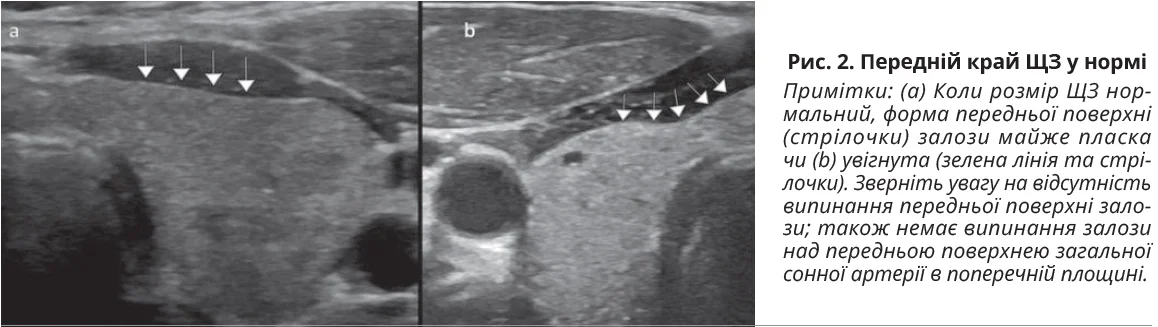

Завдяки своєму колоїдному вмісту нормальна ЩЗ має гіперехогенний вигляд порівняно з підпід’язиковими м’язами. Нормальну ехотекстуру ЩЗ визначають як рівномірну та гомогенну гіперехогенну. Вона має чітко окреслені периферичні межі. Передній край ЩЗ є пласким або увігнутим, як представлено на рисунку 2.